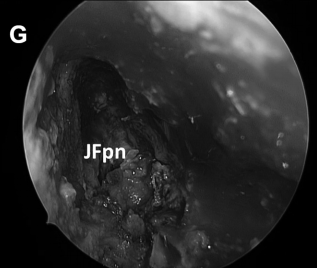

▼然后肿瘤被切除。在图8G中,可见肿瘤基底部暴露,并且颈静脉孔神经部组织可以通过组织质地来区分。

▼首先应用一层TachoSil脂肪移植物覆盖(图8H)

▼然后使用中鼻甲粘膜进行(图8I)进行闭合。

CD,斜坡凹陷;S,蝶鞍;SR,蝶嘴;T,肿瘤。